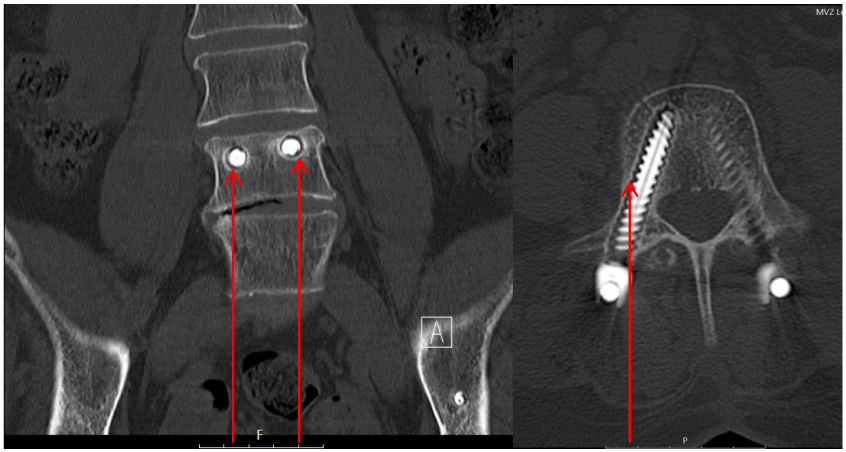

Revision surgery was necessary in two patients during the hospital stay. One patient with a FFP 4b type fracture presented a drop foot, grade 4 according to BMRC (British Medical Research Council), due to a malposition of the sacroiliac screws. Due to progressive paralysis (grade 3) and progressive Trendelenburg sign, revision surgery was performed five days after primary surgery. 1 year after revision surgery the paralysis was declining (grade 4), there was no pain (Figure 4 [Fig. 4]).

Figure 4: FFP 4b type fracture. The red arrows show the malposition of the sacroiliac screws anterior to the ala. The short red line shows the course of the L5 nerve. The conflict between the screws and the nerves is obviously.